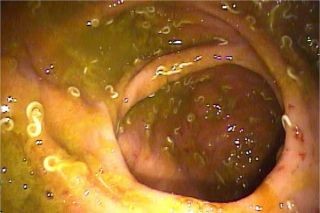

سرطان روده و کولیت اولسراتیو چه تفاوت هایی با هم دارندسرطان روده از سلولهای غیر طبیعی تشکیل شده است که به بخش‌های دیگر بدن گسترش می یابد اما در کولیت اولسراتیو التهاب حاد یا مزمن غشای پوشاننده سطح داخلی روده اتفاق افتاده است و این وضعیت به نواحی دیگر بدن گسترش نمی یابد.

کولیت اولسراتیو باعث التهاب روده بزرگ می‌شود و بدیهی ترین تاثیر این بیماریف علائمی مانند اسهال و دل درد است. با این حال کولیت اولسراتیو یا کولیت زخمی خطر سرطان روده را هم ممکن است افزایش دهد. اینجا با ارتباط بین بیماری کولیت اولسراتیو و سرطان روده بیشتر آشنا می شوید.